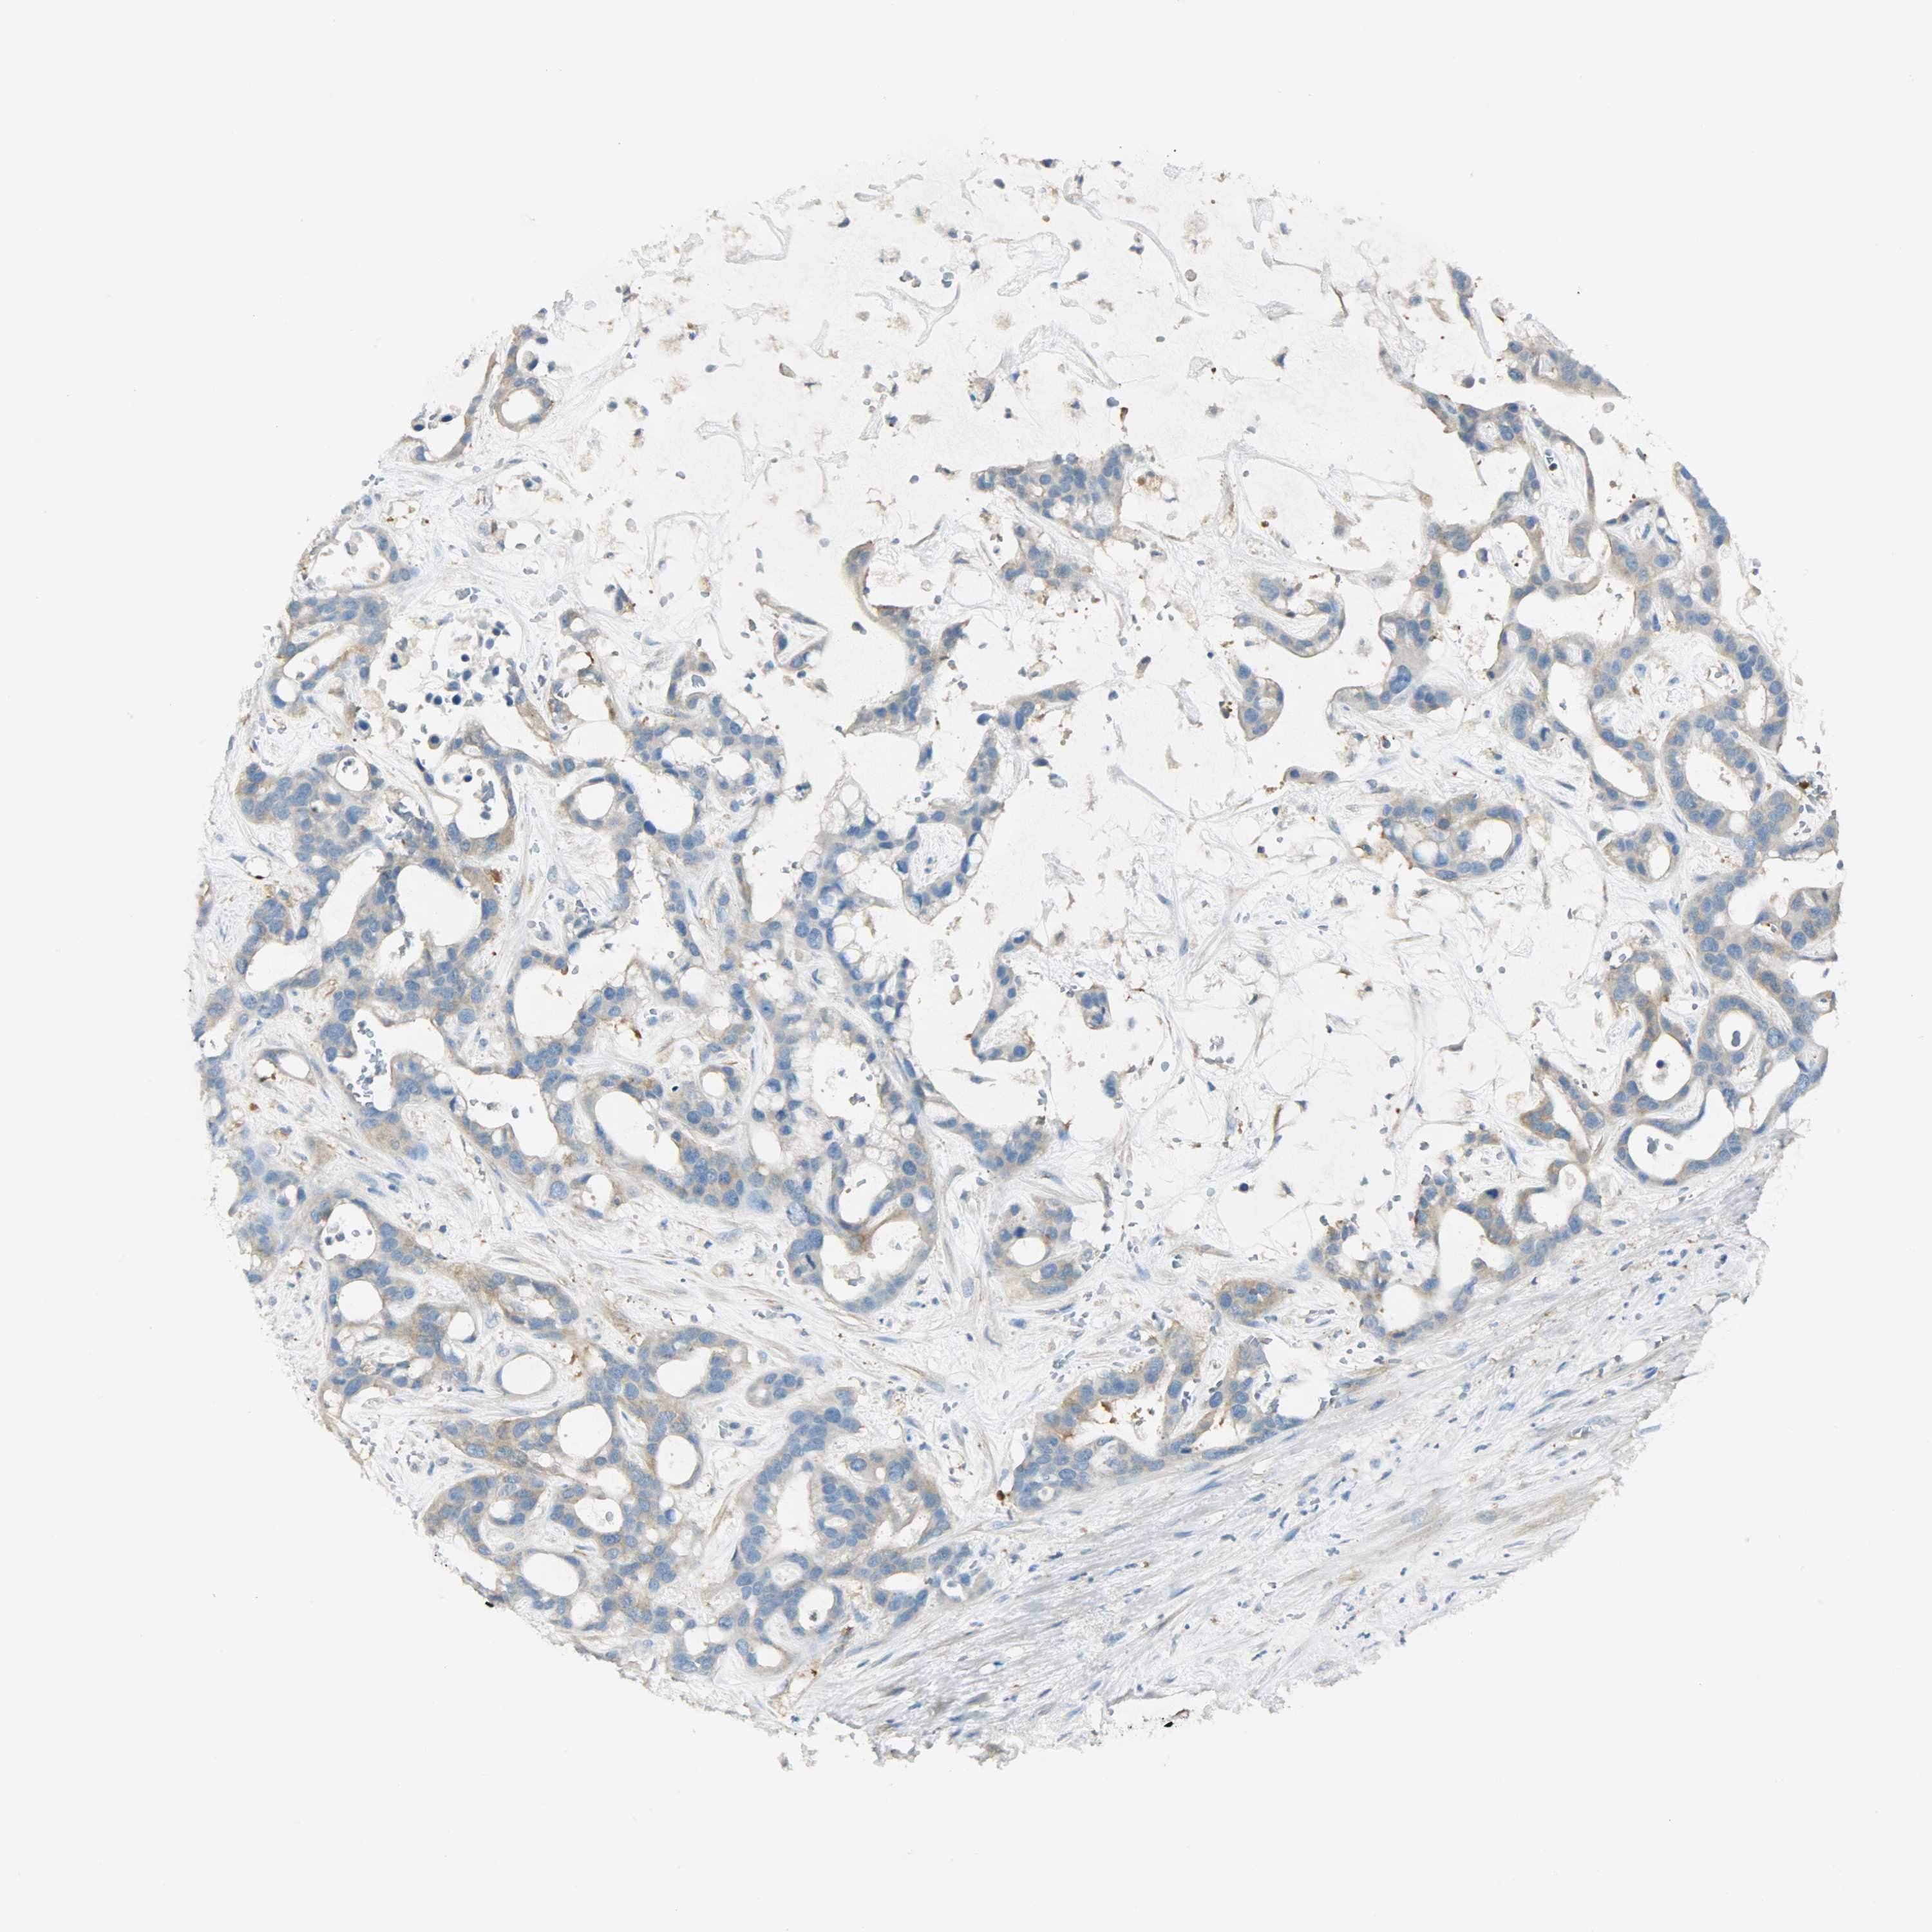

LIVER CANCER - Protein expressioni

A mouse-over function shows sample information and annotation data. Click on an image to view it in a full screen mode. Samples can be filtered based on level of antibody staining by selecting one or several of the following categories: high, medium, low and not detected. The assay and annotation is described here.

Note that samples used for immunohistochemistry by the Human Protein Atlas do not correspond to samples in the TCGA dataset.

Antibody stainingi

Antibody staining in the annotated cell types in the current human tissue is reported as not detected, low, medium, or high, based on conventional immunohistochemistry profiling in selected tissues. This score is based on the combination of the staining intensity and fraction of stained cells.

Each image is clickable and will lead to virtual microscopy that enables deeper exploration of all samples and also displays staining intensity scores, fraction scores and subcellular localization as well as patient and tissue information for each sample.

Antibody HPA004926

Staining

High

Medium

Low

Not detected

Intensity

Strong

Moderate

Weak

Negative

Quantity

>75%

75%-25%

<25%

None

Location

Nuclear

Cytoplasmic/membranous

Cytoplasmic/membranous,nuclear

Cholangiocarcinoma

Carcinoma, Hepatocellular, NOS